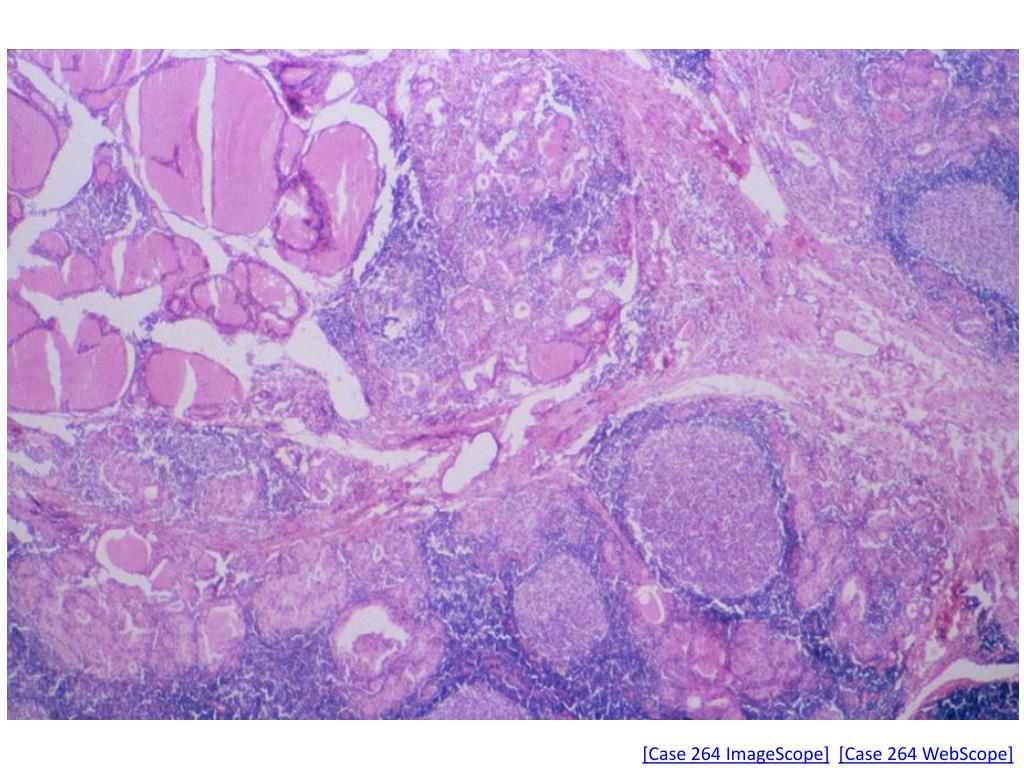

19. Case No. 264 • Clinical History: A 38 year old white female complained of a mass in the neck of several months duration. At the time of examination the thyroid was enlarged and somewhat nodular. She had no symptoms of hypothyroidism or hyperthyroidism.

20. [Case 264 ImageScope][Case 264 WebScope]

21. [Case 264 ImageScope][Case 264 WebScope]

22. [Case 264 ImageScope][Case 264 WebScope]

23. [Case 264 ImageScope][Case 264 WebScope]